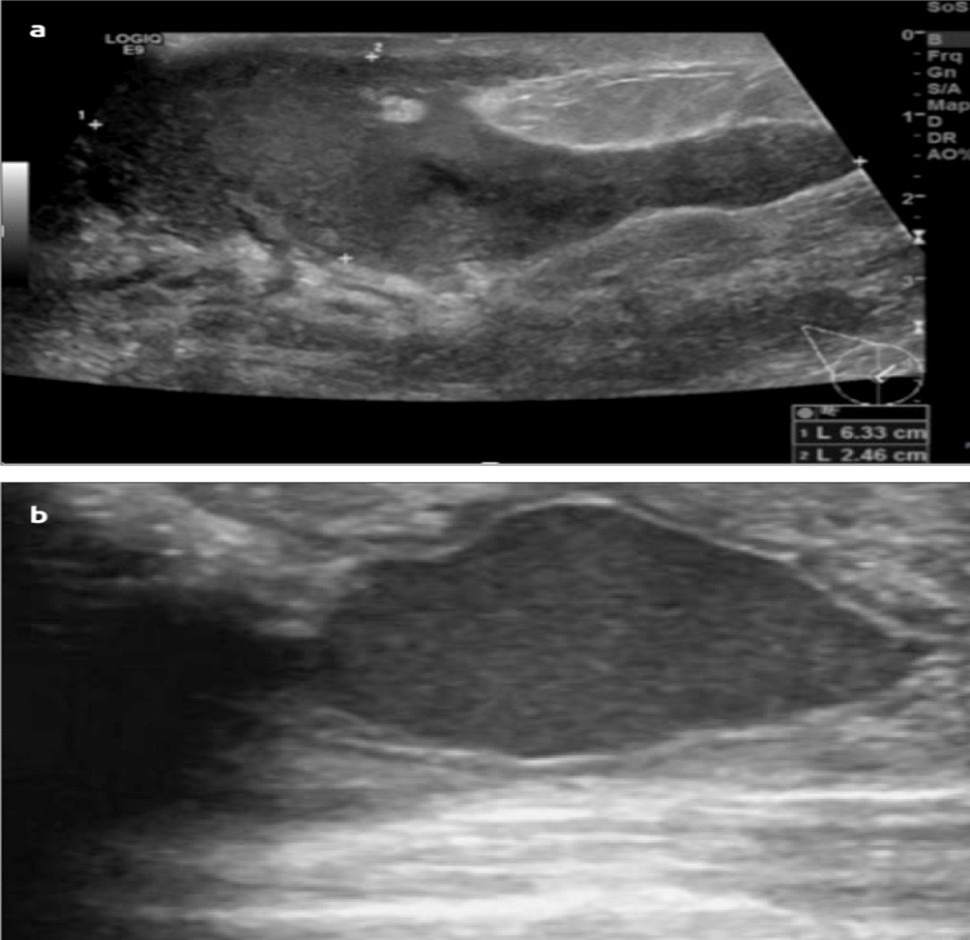

Ultra Sonogram

Depicts: An abscess is been seen as a hypoechoic lesion